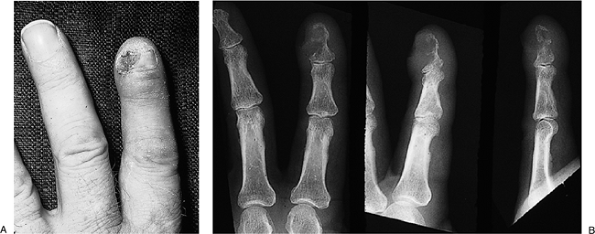

freed from the mass.P.46

Figure 3-13 (A) The enlarged terminal phalanx (arrows) of this carpenters thumb revealed a thick-walled cyst. (B) It was filled with keratin material. (C) It was easily shelled out of the pulp of the terminal phalanx. -